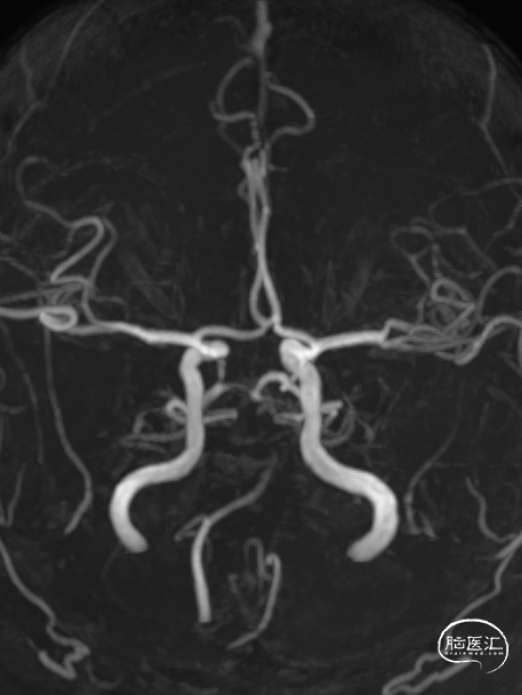

MR:双侧后循环散在急性梗死病灶(双侧小脑半球、双侧枕叶、胼胝体压部、右侧脑桥臂、桥脑右侧部及中脑被盖左侧)。MRA示:双侧椎动脉颅内段及基底动脉明显变窄。

CTA:椎基底动脉连接处重度狭窄;多发脑动脉狭窄。

举例图片,非上述病例患者